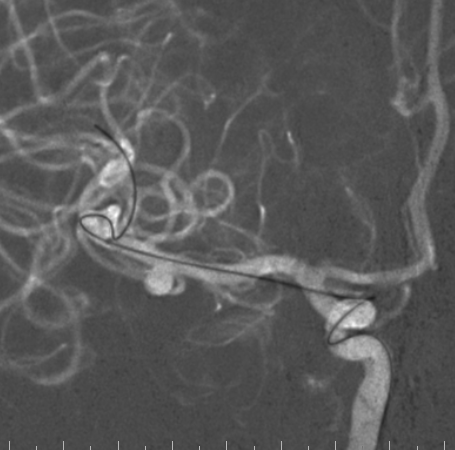

右侧颈总造影:右侧大脑中动脉瘤

右侧大脑中动脉瘤,瘤颈处发出颞支,颈宽3.79mm,瘤高3.51mm,远近端载瘤动脉直径分别为2.43mm、2.52mm。

右侧椎动脉硬膜外V2、V3段梭形扩张,前向血流通畅。